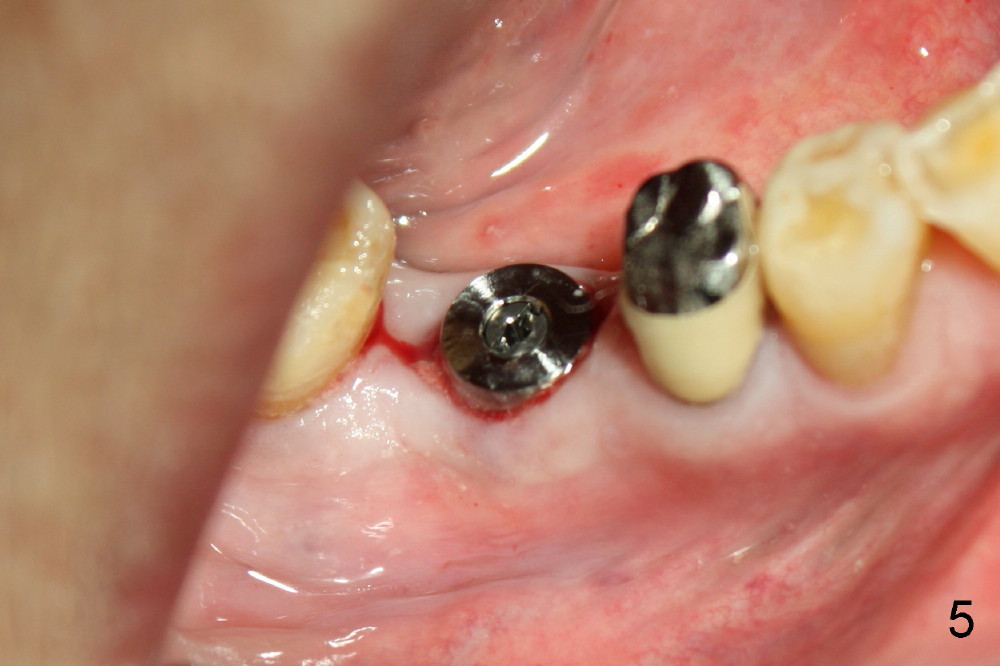

几个月前右下六根尖周炎,根管治疗无效,Amoxicillin引起全身过敏性皮炎,最后拔除。术后六周伤口愈合,牙槽骨有些吸收(图四),通过骨扩张,植入6x17mm植牙(图五,牙槽骨好像不再萎缩了,与图四相比),伤口挺密合,不需要缝线,但是不是天衣无缝,细菌食物还是会进入伤口造成感染。服用抗生素好像不是个好主意(过敏史),灵机一动:使用periodontal dressing盖住植牙(图六)。但是术后病人抱怨局部肿痛,最后还是服用灭滴灵。术后第九天,患者回诊所左上七牙冠粘固,顺便拆除右下periodontal dressing(图六),dressing下面伤口愈合了吗?还是象图二那么糟(婚纱后面新娘漂亮吗)?